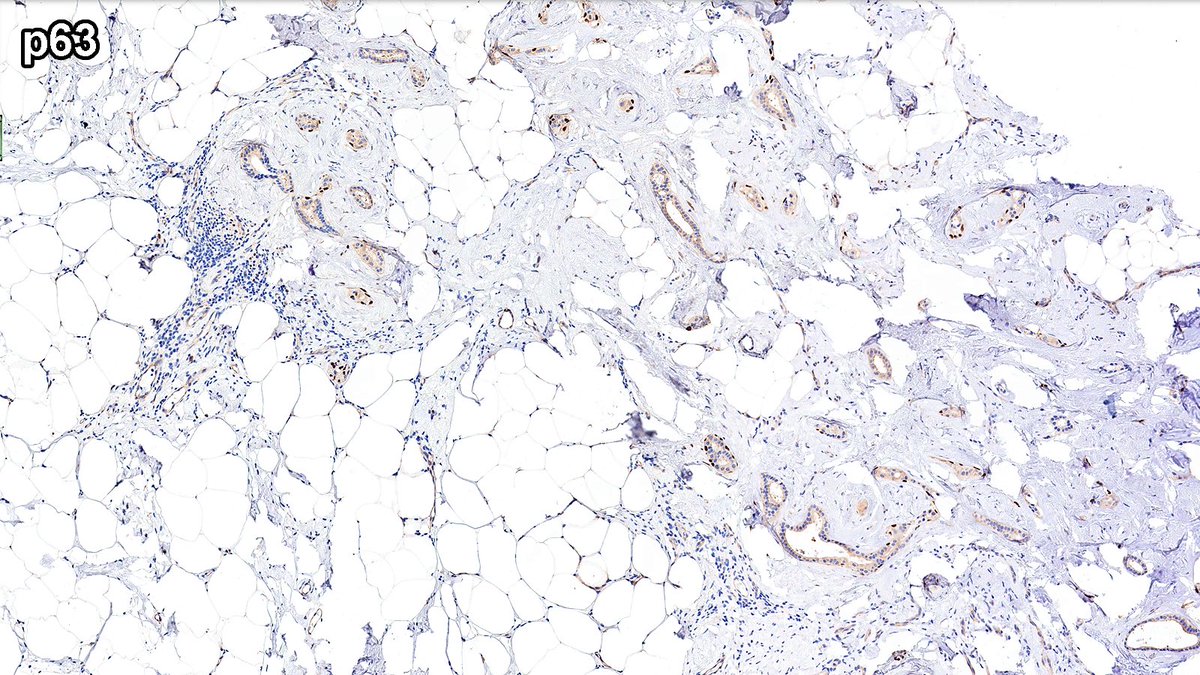

Case of Radial Scar 🗿🔬

Central fibroelastic core with entrapped glands radiating outward 🌟.

A master of masquerade, fibroelastotic nidus can simulate desmoplastic stroma—p63 shown below 👇.

#PathX #PathTwitter #breastpath